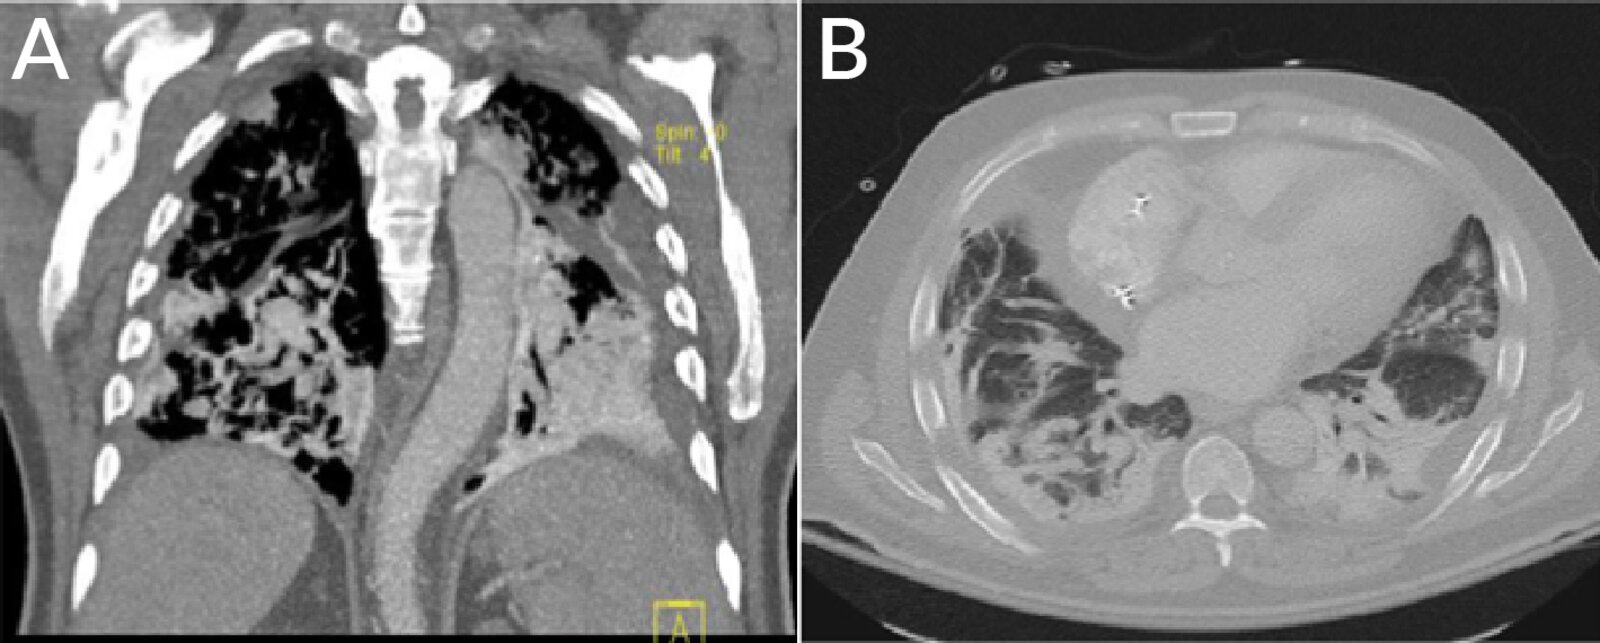

Pulmonary

• Pulmonary fibrosis

• Chronic interstitial pneumonitis

• Organizing pneumonia

• ARDS

• Solitary pulmonary mass

Pulmonary [5]

• Amiodarone-induced pulmonary toxicity (AIPT) leads to the most deaths associated with amiodarone therapy.

• Toxicity correlates more closely with cumulative dose than with serum drug levels.

• Treatment: Discontinue amiodarone and initiate corticosteroid therapy.